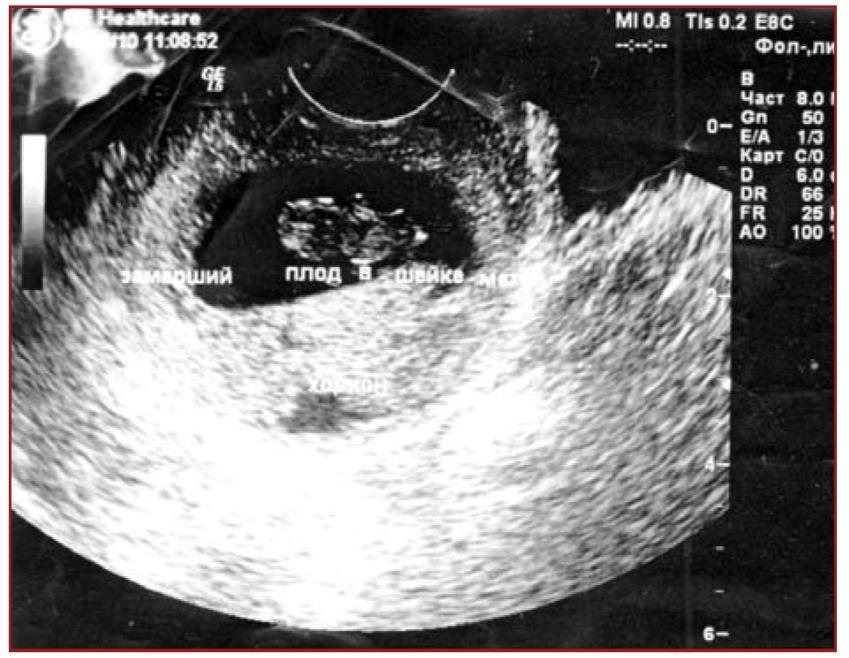

Чтобы точно установить диагноз «замершая беременность», врач может отправить беременную на ультразвуковое исследование. Это наиболее подходящий вариант,

чтобы точно определить патологию. если срок слишком маленький, то исследование проводится повторно спустя неделю.

- На ультразвуковом исследовании не слышно плодного сердцебиения, а показатели размеров матки не соответствуют сроку беременности.

Важно! Если до 7-й недели имеются подозрения на замершую беременность, то аборт откладывают до повторного ультразвукового исследования. Может случиться так, что аппарат не обнаружил жизненных функций эмбриона или врачом была допущена ошибка при расчетах сроков зачатия.

- ранний срок — неправильное расположение плодного яйца или его повреждение;

- поздний срок — отсутствие сердцебиения у плода и несоответствие его размеров сроку.

Данных УЗИ недостаточно для постановки окончательного диагноза — ЗБ. Из-за гормональных сбоев и психологических нагрузок у женщин задержка развития плода может составлять до четырех недель. В этом случае проводят повторное УЗИ через две недели. Если плод не увеличился в размерах, то это означает, что он мертв.

Показания УЗИ — это самый надёжный и достоверный показатель, подтверждающий наличие замершей беременности. Ошибки случаются только на ранних сроках беременности, когда врач может принять за пустое плодное яйцо, нормально развивающееся. В таком случае, если состояние пациентки не внушает опасений, можно подождать до 6-7 недель и повторить УЗИ. На этом сроке опытный врач при помощи современной аппаратуры уже хорошо видит эмбрион и слышит его сердцебиение.

- Ультразвуковое исследование, с помощью которого врач определяет сердцебиение плода, наличие или отсутствие живого эмбриона. Если сердцебиение не прослушивается на сроке до 8 недель – это ненадежный показатель гибели эмбриона.

Рекомендуется провести повторное УЗИ через неделю. - Лабораторное исследование крови для определения уровня ХГЧ (хорионического гонадотропина человека). При значительном снижении ХГЧ можно с большой долей вероятности утверждать, что беременность не развивается.

Такой диагноз можно поставить после прохождения УЗИ .

По УЗИ не определяется сердцебиение и шевеление плода. Эмбрион по размерам меньше, чем должен быть. Может выявляться пустое плодное яйцо (анэмбриония). На УЗИ женщина может быть направлена при подозрении на замершую беременность, либо это может быть выявлено при плановом проведении УЗИ (срок первого планового УЗИ – 10–14 недель).